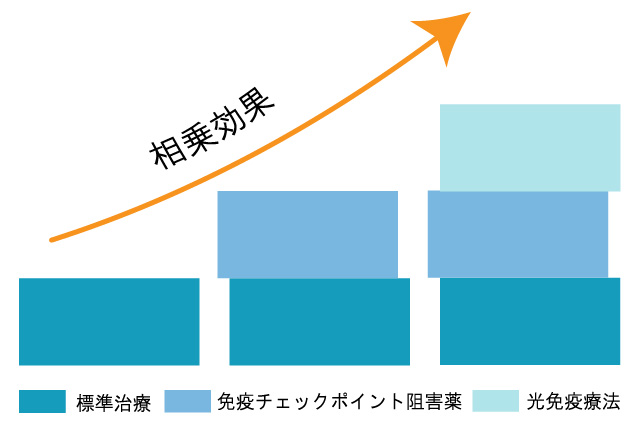

併用できる治療

他の治療との併用が可能です。標準治療はがん治療において非常に効果的ですが、治療法ごとに適用範囲や強みが異なることも事実です。それぞれの治療法の相乗効果を期待し、複合的な治療を提供することも可能です。

効果を向上させる複合治療

- 光免疫療法による腫瘍細胞の死と抗原の放出は、免疫システムを「目覚めさせる」効果があります。これにより、通常は「見過ごされがち」な腫瘍細胞に対する免疫システムの識別能力が向上します。

- PD-1阻害剤による介入は、この「目覚めた」免疫応答が腫瘍細胞に作用するための障害を取り除きます。つまり、光免疫療法で活性化された免疫応答が、PD-1阻害剤によりさらに強化され、効率的に腫瘍を攻撃することができるようになります。

これらの理由から、光免疫療法とPD-1阻害剤は組み合わせて使用すると、単独で使用する場合に比べて腫瘍に対する攻撃力が強化される可能性があります。

標準治療との併用は可能です。標準治療と併用する事で双方に良い相乗効果が期待出来ます。現在通われている病院の治療のご予定を確認させて頂きながら当院の治療スケジュールを組ませて頂きますのでご安心して通っていただけます。